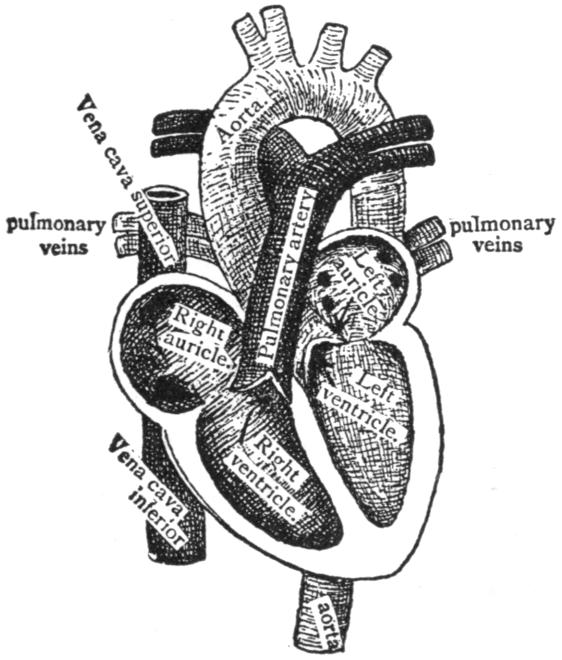

| V. | The Circulation | H 51 |